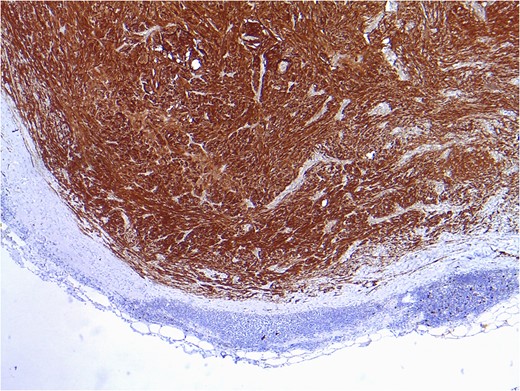

Positive result after immunohistochemical study for vimentin and protein S100, compatible with intranodal schwannoma.

Among the benign lesions, the most important distinction must be made with the miofibroblastoma, whose characteristics include hemorrhage focuses and areas of starry arranged collagen. While miofibroblastomas show a positivity result for actin immunohistochemistry, they do not do it for S100 protein, whose positivity is strongly linked to the schwannomas. In our case, the immunohistochemical consistently oriented in the direction of these latter.